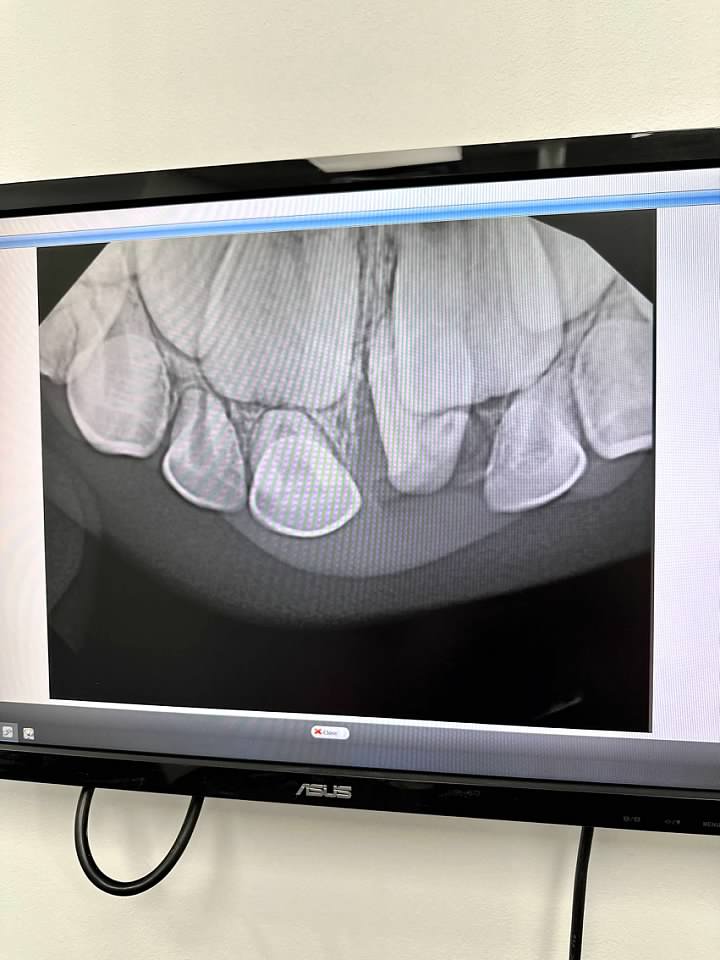

Finn had to have oral surgery because he had an extra tooth growing in. We found out this extra tooth was the reason that he lost his first baby tooth prematurely. He did absolutely amazing, but I was a nervous wreck because neither of my kids ever had to have anesthesia or an IV.